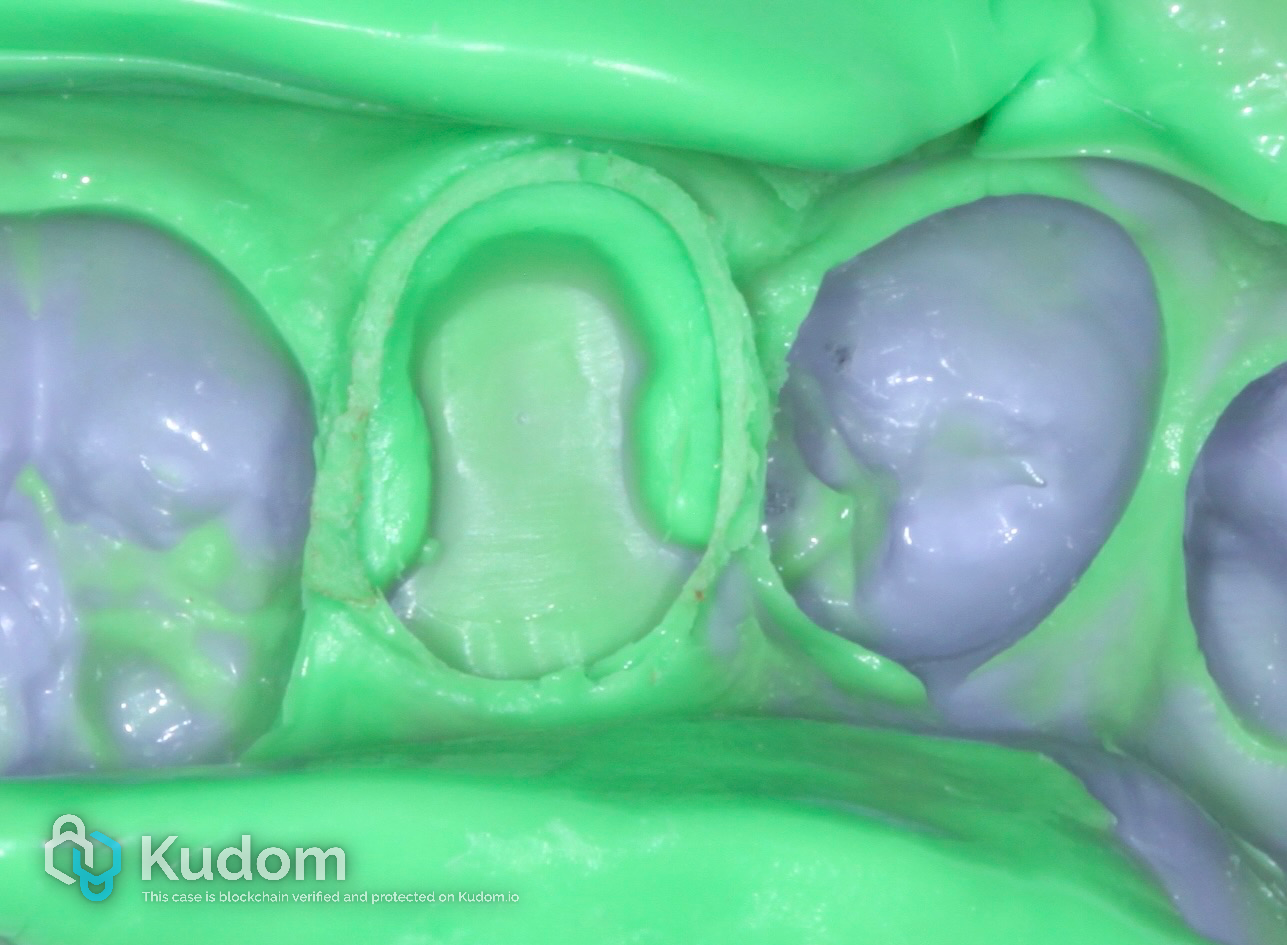

Impression

Fig. 10